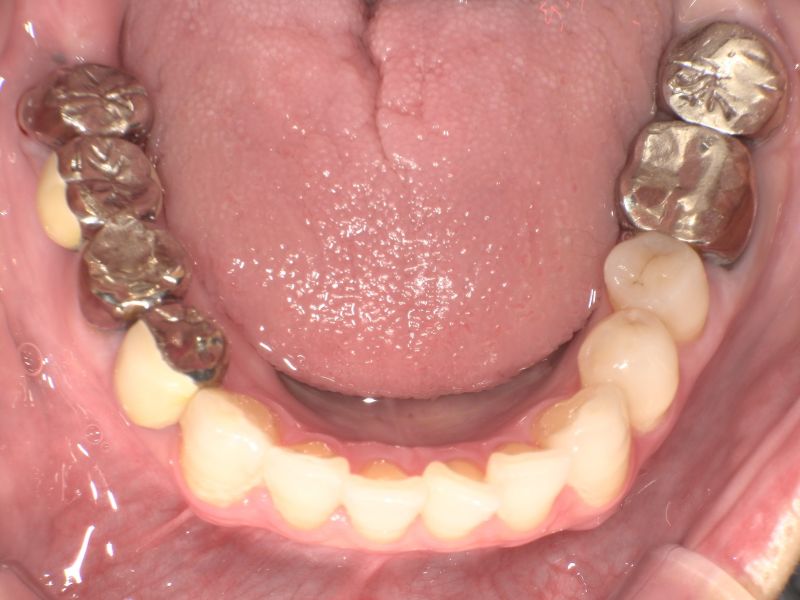

主訴:下の銀歯をセラミックに変えたい

上部構造:全てフルジルコニア

費用:¥524,000

治療期間:2ヶ月

副作用・リスク:銀歯のみ変更できる場合もありますが、歯の状態により根の治療やう蝕治療、歯周病の治療が必要になる場合があります。